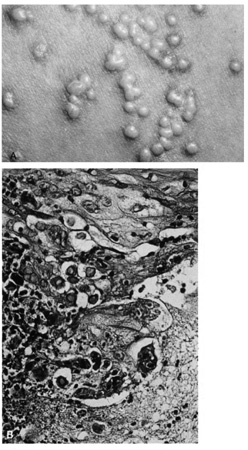

Lesions of molluscum contagiosum often affect the periorbital and lid skin as 1- to 3-mm domeshaped papules with a small central dell. This large pox virus multiplies in the cytoplasm, and, histologically, homogeneous purple intracytoplasmic inclusion bodies (molluscum bodies) are seen in an acanthotic epidermis (see Fig. 7).

Fig. 7. Molluscum Contagiosum—A. Umbilicated lesions typical of molluscum contagiosum on the upper lid of a child. Infection near the edge of the lid may cause a toxic follicular conjunctivitis. B. Low-power photomicrograph demonstrating crater shape of excised lesion (hematoxylin and eosin stain). C. High-power photomicrograph illustrating the large clumps of eosinophilic viral inclusions in the epithelial cells (“molluscum bodies“) (hematoxylin and eosin stain). (Photos courtesy of William Morris, M.D.)

Verruca vulgaris (warts) are caused by a variety of papilloma viruses and may present as small papules with a digitated surface or elongated filiform warts around the eyes. Histologically, they demonstrate varying degrees of massive papillomatosis, hyperkeratosis, and acanthosis with parakeratosis and collections of serum in the stratum corneum at the tips of the digitations (Fig. 8). In early warts, the keratinocytes in the granular layer and just beneath the granular layer are vacuolated with condensation and clumping of dark-staining keratohyaline granules and occasional eosinophilic inclusion bodies in the nuclei.

Fig. 8. Verruca Vulgaris—A. Low-power photomicrograph illustrating papillomatous growth with a fibrovascular core, hyperkeratosis, and acanthosis (hematoxylin and eosin stain). B. High-power photomicrograph demonstrating intranuclear viral inclusion (black arrow) (hematoxylin and eosin stain). (Photos courtesy of William Morris, M.D.)